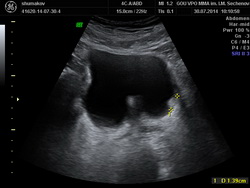

Из анамнеза: в июле 2014 года после физической нагрузки отметил появление крови в моче с бесформенными сгустками. В поликлинике по месту жительства при ультразвуковом исследовании выявлена аденома предстательной железы. Консультирован в клинике урологии УКБ№2 Первого МГМУ им. И.М. Сеченова, при УЗИ заподозрена опухоль мочевого пузыря. Выполнена МРТ органов малого таза, по данным которой по левой боковой стенке мочевого пузыря определяется экзофитное образование размерами 0,9х0,8х0,7мм. Также выявлена аденома предстательной железы. Госпитализирован в плановом порядке для оперативного лечения

Рис№1. УЗИ мочевого пузыря и предстательной железы.